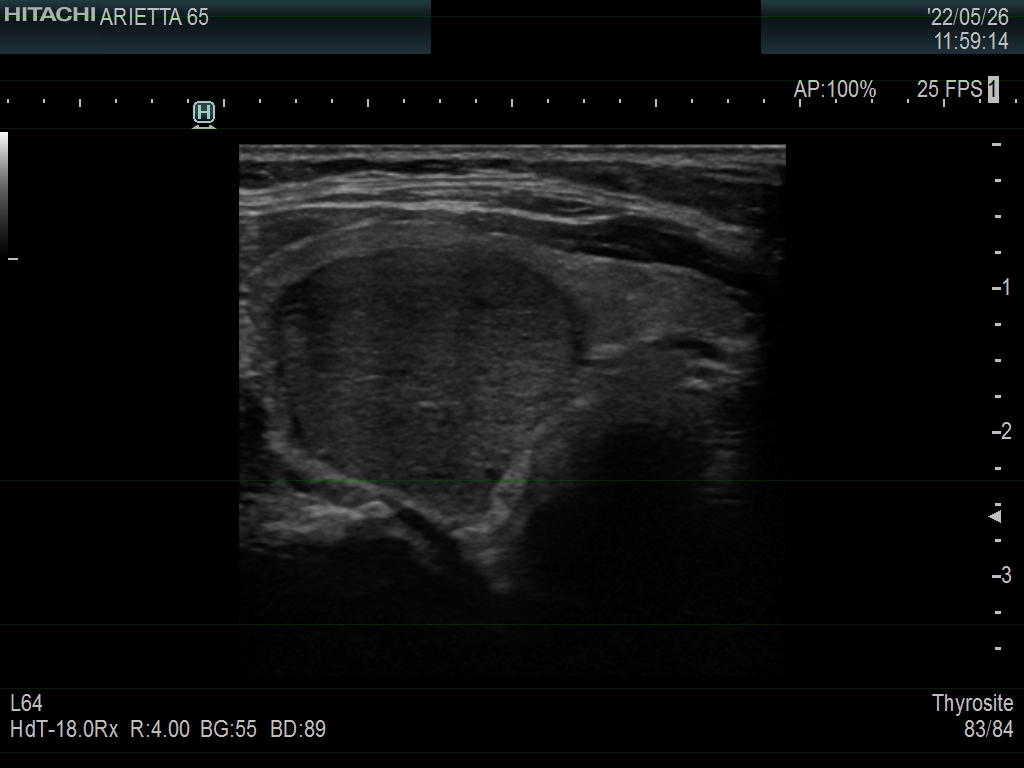

Ultrasonography. The thyroid was echonormal. There was a moderately hypoechoic nodule in the right lobe. The nodule has halo and presents with a combined perinodular and intranodular blood flow. The latter was irregularly increased.

The presentation of the nodule is not very suspicious. Halo sign is a rare finding in medullary cancers.

The classification of the nodule depends on the judgement of nodule borders. If it is regarded as irregular, then the lesion is an EU-TIRADS 5 one. However, if we judge the borders as non-lobulated, then the lesion is an EU-TIRADS 4 nodule. According to the EU-TIRADS, FNA is indicated in both cases because the largest diameter of the nodule exceeds 15 mm.